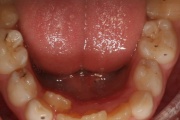

Hambad

Ruumipuudus eesmiste hammaste osas